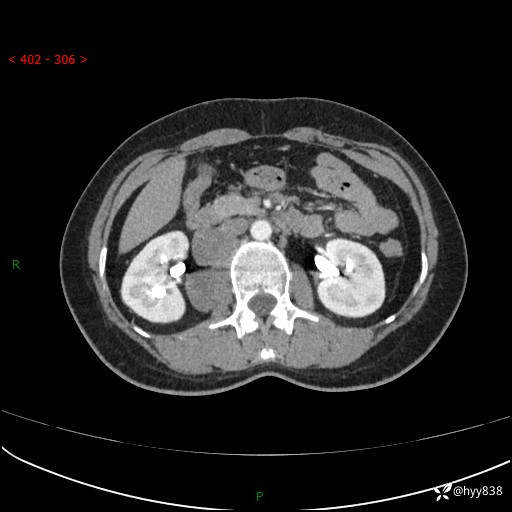

现在都流行跨界,病变也不例外,从腹膜后长到胸腔了---结果公布~

主诉:体检发现右侧腹膜后肿物1天

简要病史:患者于1天前因体检发现右旁肾占位,无肉眼血尿,无畏寒发热,无咳嗽咳痰,无腰腹部疼痛不适,无尿频尿急症状,起病来,患者未行特殊治疗,为求进一步诊治,门诊以"右侧腹膜后肿物"收治入院。 发病来患者精神、饮食、睡眠良好,小便如上,大便正常,体重无明显变化。

临床诊断:腹膜后肿物

上腹部CT增强(动脉期+实质期)(外院平扫)